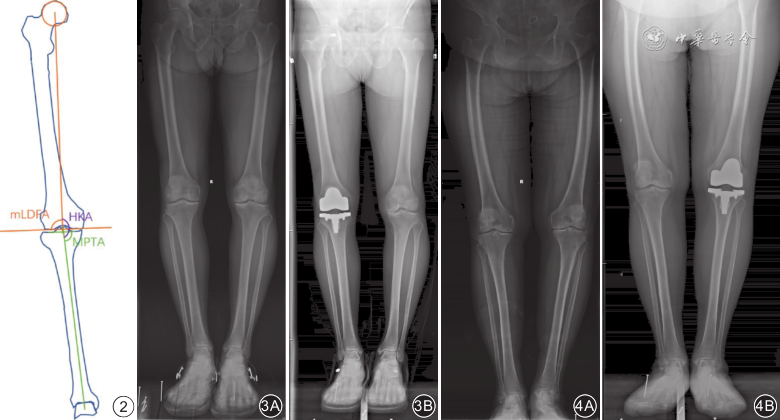

在术前及术后3个月下肢全长负重位X线片上,测量2组患者手术前后HKA、机械股骨远端外侧角(mechanical lateral distal femoral angle,mLDFA)和MPTA。HKA为股骨头拟合圆的圆心到膝关节中点连线与膝关节中点到距骨中点连线相交的内侧角。mLDFA为股骨头拟合圆的圆心到膝关节中点连线与股骨远端内外侧髁最远端连线相交的外侧角。MPTA为膝关节中点与距骨中点连线与胫骨内外侧平台最低点连线相交的内侧角。见图2。

注:HKA为髋膝踝角;mLDFA为机械股骨远端外侧角;MPTA为胫骨近端内侧角;KA为运动学对线;MA为机械学对线;TKA为全膝关节置换术

组间比较:术前HKA、mLDFA、MPTA以及术后HKA、mLDFA的差异均无统计学意义(P值均 > 0.05);KA组术后MPTA小于MA组,差异有统计学意义(P = 0.002)。组内比较:2组患者HKA在术后3个月均大于术前,MA组MPTA在术后3个月也大于术前,差异均有统计学意义(P值均 < 0.01);而KA组的MPTA和2组的mLDFA手术前后差异均无统计学意义(P值均 > 0.05)。见表2及图3、4。